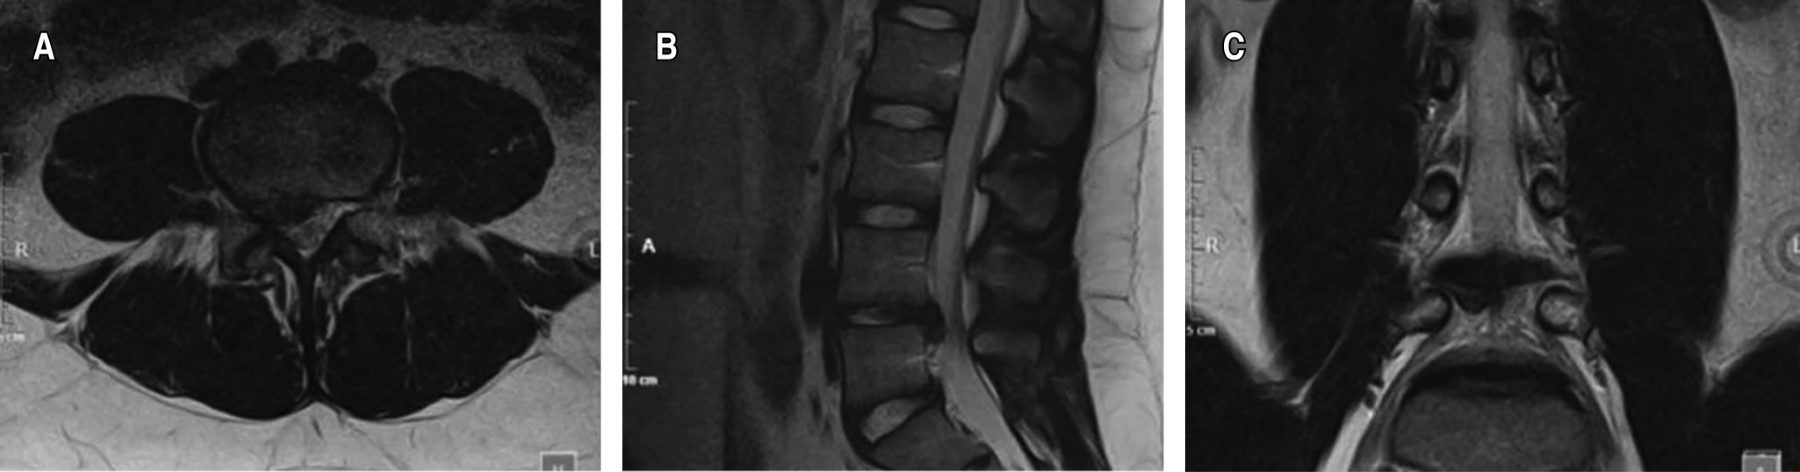

Figure 2